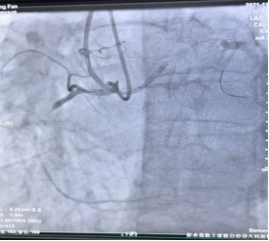

第2例是一位高龄男性患者,84岁冉爷爷1月前因“突发胸痛”就诊,诊断为急性心肌梗死,术中造影提示罪犯血管为前降支,右冠近端完全闭塞,考虑慢性闭塞性病变,行急诊PCI后治疗患者好转出院,医生建议患者择期在IVUS指导下行右冠支架植入术。同样,在陈元友主任的指导下,王欣医师行双侧造影,在钢丝通过闭塞病变后,将IVUS导管放置在血管远端,采取自动回撤模式,可见闭塞处主要为纤维病变,测得管腔最狭窄面积为2.5mm2,病变长度达34.7mm,已经达到介入手术指征,在右冠长病变处成功植入1枚支架,术后IVUS测得最狭窄处管腔面积为6.2mm2,,IVUS及冠脉造影提示术后支架贴壁良好,远端血流恢复正常,患者术后恢复良好。见图2、图3。

图3(左图为术前,右图为术后)